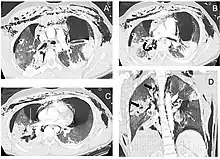

| Reconstruction of the trachea and bronchi with x-ray computed tomography showing disruption of the right main bronchus with abnormal lucency (arrow)[1] | |

Chest x-ray is the initial imaging technique used to diagnose TBI.[17] The film may not have any signs in an otherwise asymptomatic patient.[15] Indications of TBI seen on radiographs include deformity in the trachea or a defect in the tracheal wall.[17] Radiography may also show cervical emphysema, air in the tissues of the neck.[2] X-rays may also show accompanying injuries and signs such as fractures and subcutaneous emphysema.[2] If subcutaneous emphysema occurs and the hyoid bone appears in an X-ray to be sitting unusually high in the throat, it may be an indication that the trachea has been severed.[4] TBI is also suspected if an endotracheal tube appears in an X-ray to be out of place, or if its cuff appears to be more full than normal or to protrude through a tear in the airway.[17] If a bronchus is torn all the way around, the lung may collapse outward toward the chest wall (rather than inward, as it usually does in pneumothorax) because it loses the attachment to the bronchus which normally holds it toward the center.[6] In a person lying face-up, the lung collapses toward the diaphragm and the back.[23] This sign, described in 1969, is called fallen lung sign and is pathognomonic of TBI (that is, it is diagnostic for TBI because it does not occur in other conditions); however it occurs only rarely.[6] In as many as one in five cases, people with blunt trauma and TBI have no signs of the injury on chest X-ray.[23] CT scanning detects over 90% of TBI resulting from blunt trauma,[3] but neither X-ray nor CT are a replacement for bronchoscopy.[6]